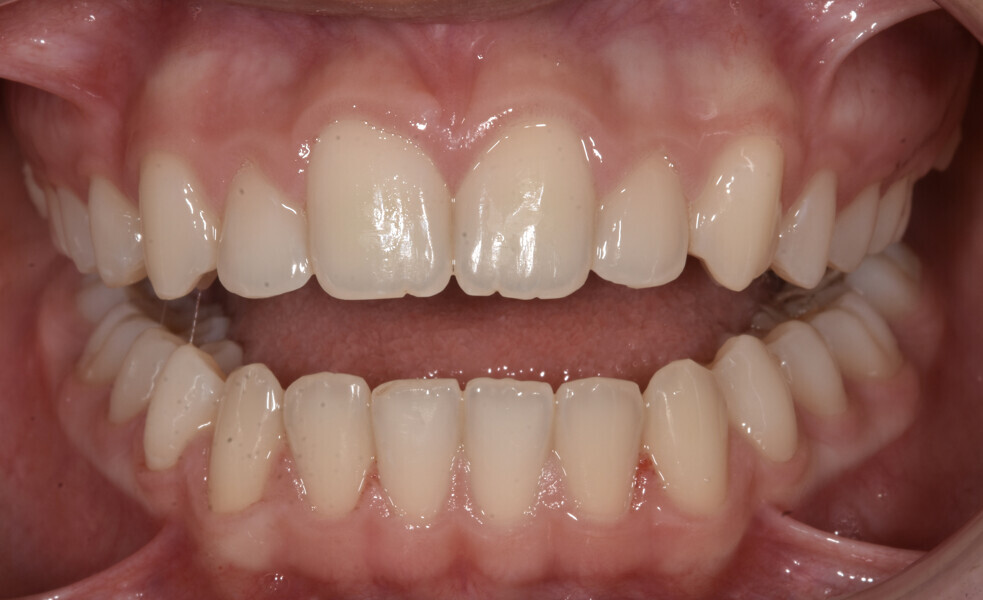

Fig. 2: Facial and intra-oral photographs after treatment with fixed orthodontic appliances.

Despite the achievement of an ideal occlusion and aligned arches by following the basic orthodontic guidelines and fulfilment of the treating dentist’s checklist, the patient came back complaining. She and her mother were dissatisfied with the smile aesthetics, angulation and buccolingual inclination of the maxillary anterior teeth, and reverse smile line.

The patient presented at the age of 14 as follows (Figs. 12 & 13):

Class I occlusion;

midlines coinciding with that of the face;

aligned arches with minor malpositions (mainly concerning the maxillary anterior teeth);

minor Bolton discrepancy (anterior discrepancy of 0.51 mm mandibular excess; total discrepancy of 0.46 mm); and

straight facial profile with slightly short upper lip.